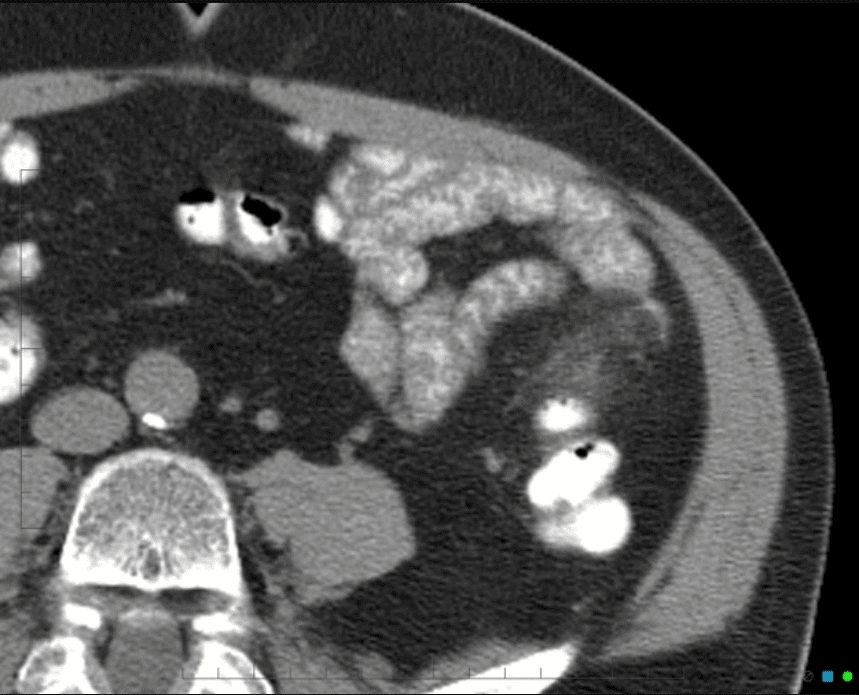

Viêm túi thừa

Viêm túi thừa - Ảnh 5

» Thông tin: Nam giới – 25 tuổi.

» Lâm sàng: Đau hố chậu trái.